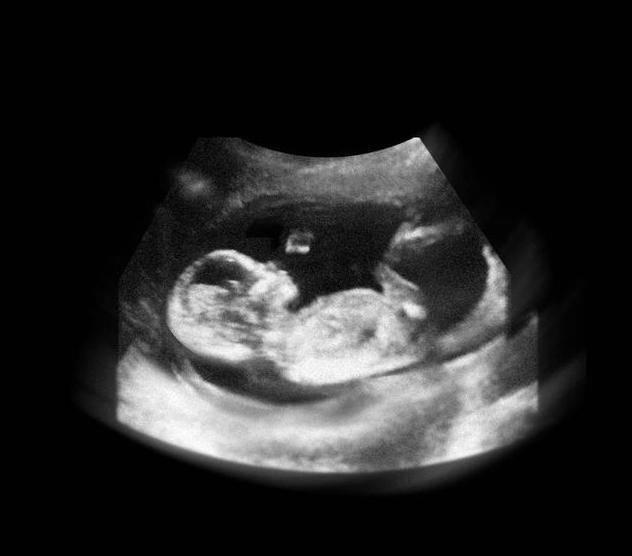

在上图可见是个双胎妊娠,胎儿具有一个很大的头,和身材很不对称,是不是跟出生后的胎宝宝有点像了?其实此时的头部比例更悬殊,宝宝的额面部器官发育很明显,心脏也开始了跳动,出现了胎心,此时做B超,可见胎心胎芽。